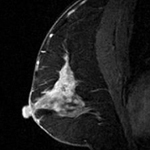

代表的な検査内容:「乳腺MRI」「下腹部精密MRI」「乳腺超音波検査」「マンモグラフィー」